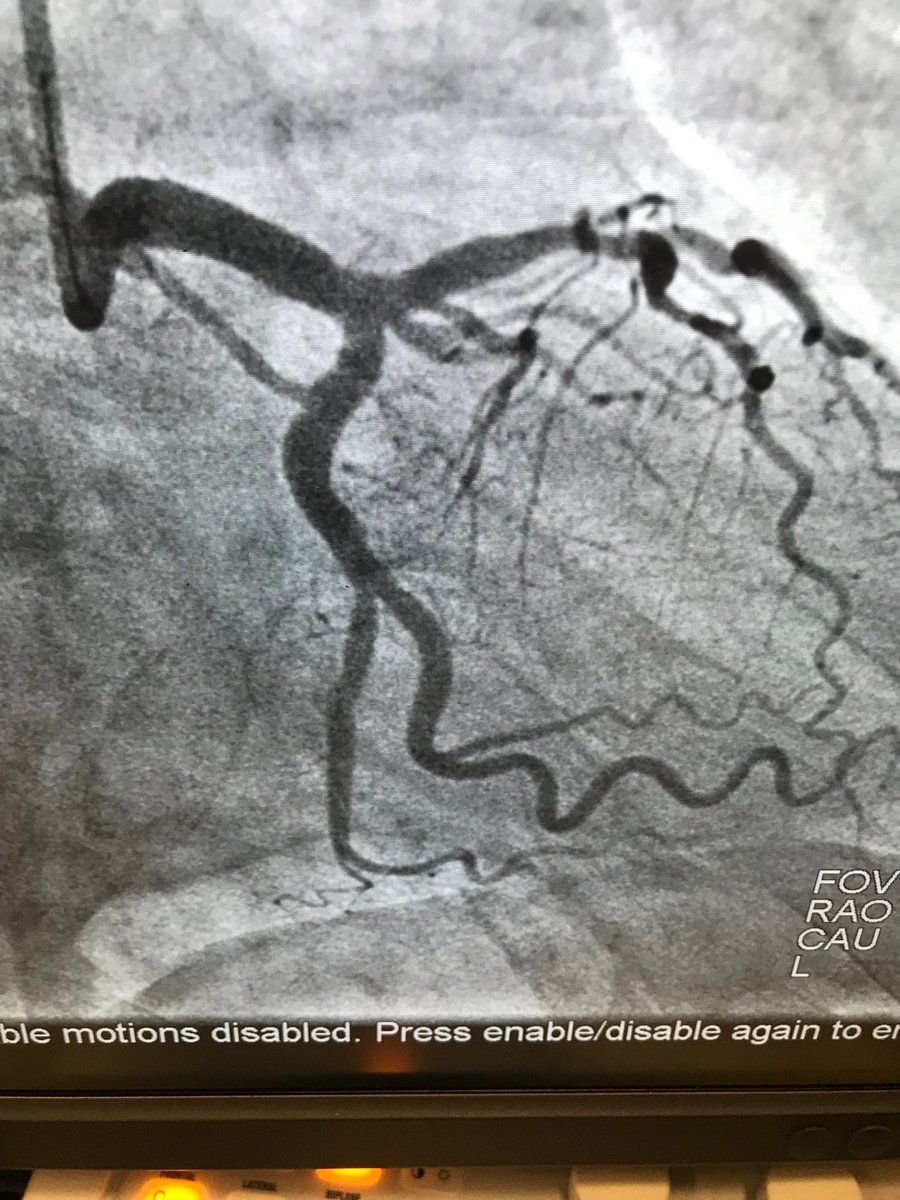

45f #cardiotwitter #safefemoral ,2 hrs symptoms,3am case, #stemi stent into left main from LAD.no#shock ,no#impella. EF40.#alifesaved

istentem's tweet image. 45f #cardiotwitter #safefemoral ,2 hrs symptoms,3am case, #stemi stent into left main from LAD.no#shock ,no#impella. EF40.#alifesaved